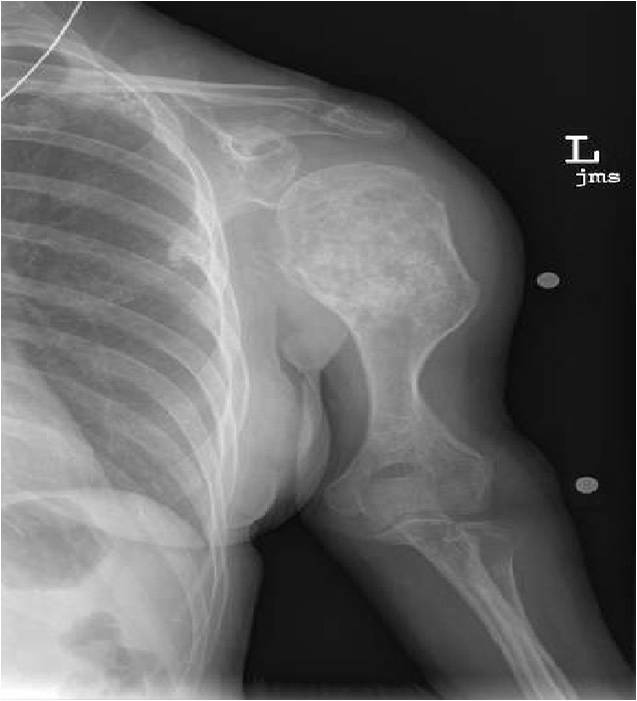

- Localized, radiolucent defect usually with punctate calcifications

- Calcifications are typical but not always present

- Matrix may demonstrate various degrees of calcification

- Calcifications are stippled, punctate, popcorn like calcifications and “Ring and Arc” calcifications

Plain X-Ray:

- Geographic lytic lesion

- Central often metaphyseal in long bones

- Expansile remodeling with thinned cortex

- Chondroid matrix with calcifications in majority of tumors

- Approximately 20% have limited or no calcifications

Ring and Arc Calcifications Minimal Endosteal Scalloping Cortex Intact No Soft Tissue Component No Periosteal Reaction

Ring and Arc Calcification No Endosteal Scalloping

Metaphyseal Tumor Heavy Calcifications Ring and Arc Pattern of Calcifications Minimal Endosteal Scalloping No Cortical Destruction No Periosteal Reaction No Cortical Destruction No Soft Tissue Component